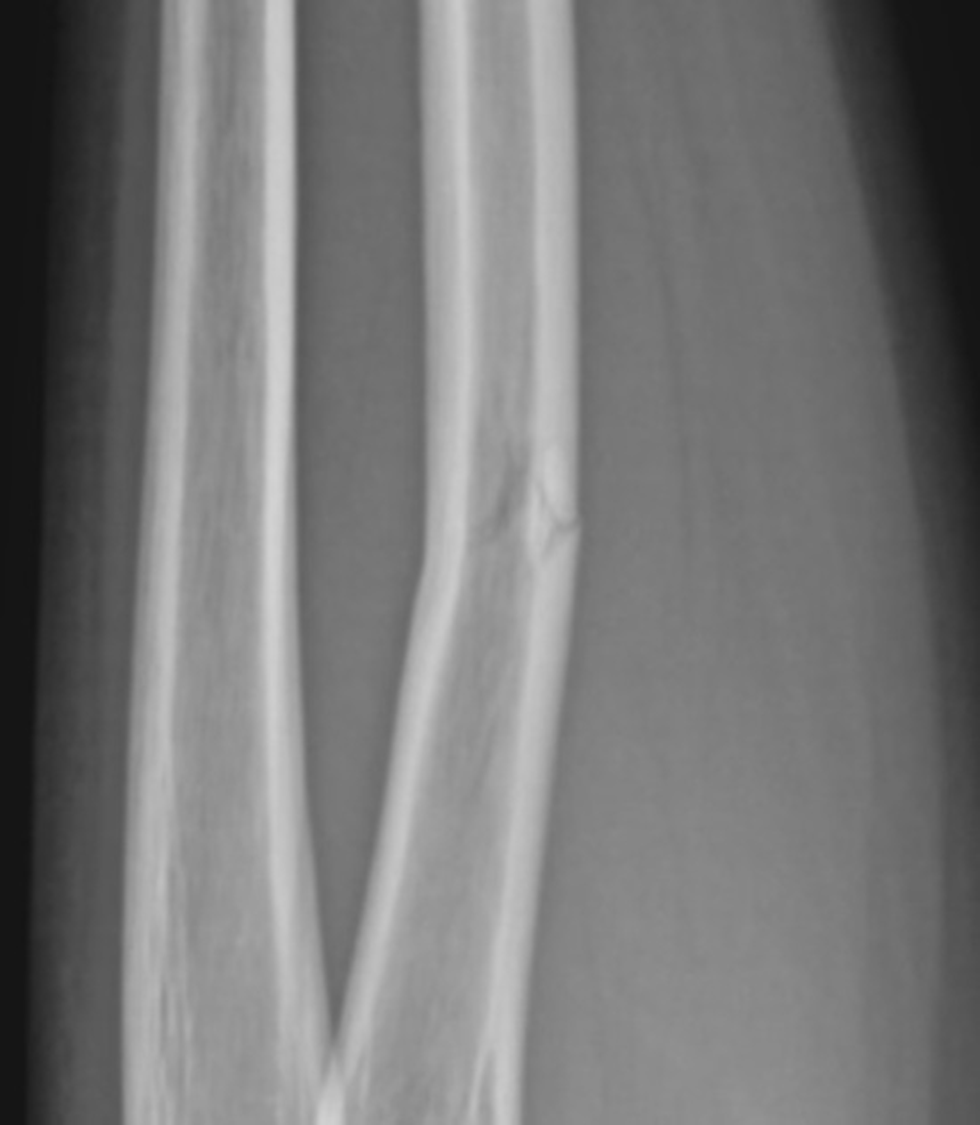

What type of fx is this

incomplete